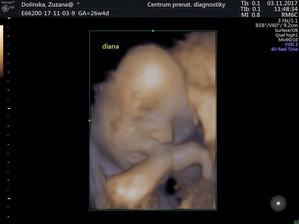

Nase dvojicky